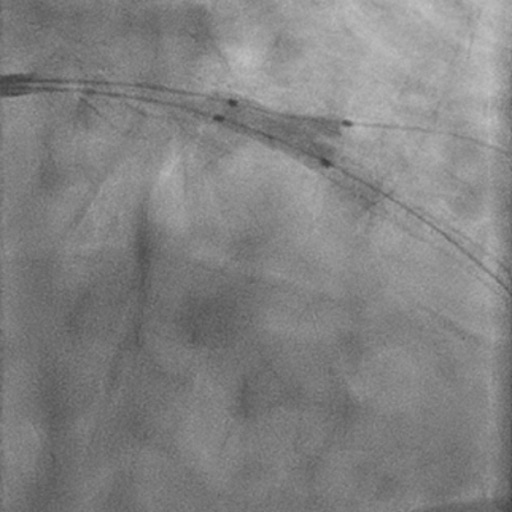

Primary PCI of Right Coronary Artery

Primary PCI and direct implantation of two overlapping DES (Onyx Frontier 2.5 x 30 mm and Onyx Frontier 3.0 x 12 mm).

Baseline